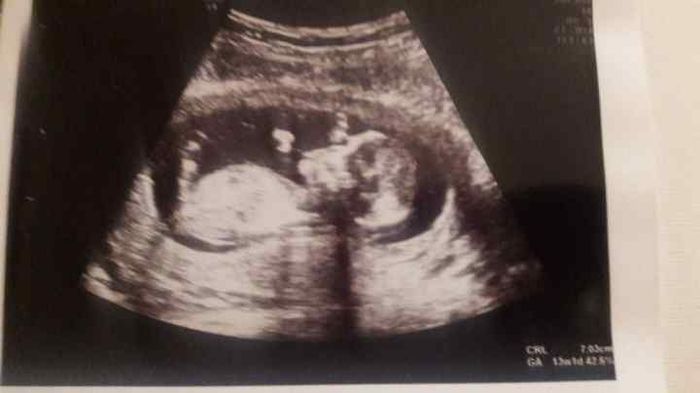

2175 giorni faCiao ragazze sono di 13+3.Secondo voi di che sesso è il feto? So che alcune di voi riescono a capirlo da una foto. Mi aiutate?Giusto una curiosità, grazie